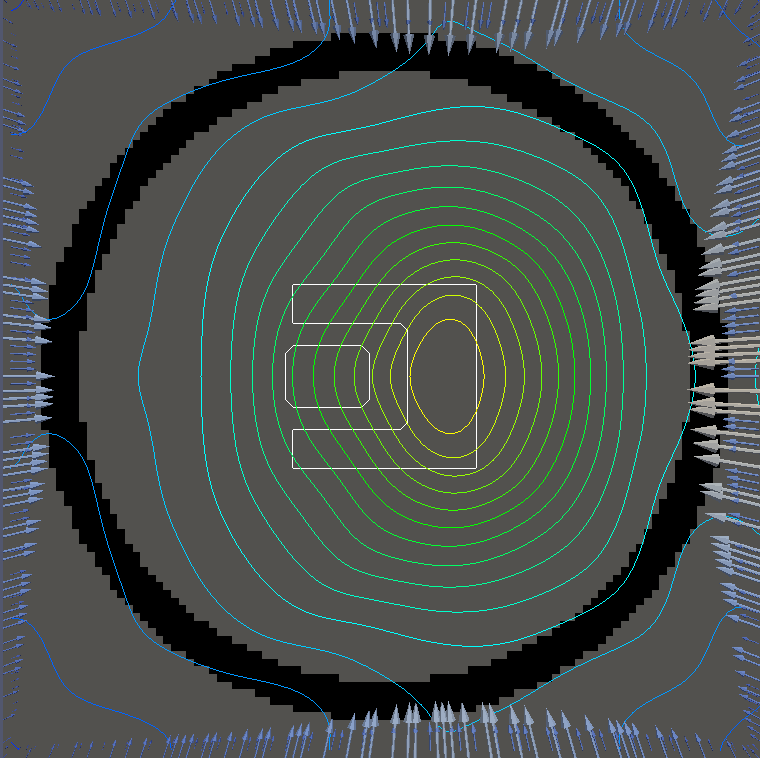

For testing, we use three tumor/risk region regions similar to those in [13]. Specifically, we define the regions in Table 3 and are shown in Figure 1; the void region is shown in black and the tumor and risk regions are traced in white. In the basic target case, seen in Figure 1(a), the tumor region is a box, as is the risk region. The second, intermediate target case, seen in Figure 1(b), involves an L-shaped tumor around a box-shaped risk region. Finally, the complex target case in Figure 1(c) involves a C-shaped tumor around a risk region.

Figure 2 shows the optimal boundary source term for both and The vectors shown on the boundary are the time-integrated values of normalized and then scaled by In Figures 2(a), 2(c), and 2(e) (corresponding to ), the isolines are spaced at intervals of the maximum of the desired dose (here, 5). In the intermediate and tracking cases, we see that relatively low dose levels are attained, primarily due to the high penalty to any dose deposited in the risk region. In Figures 2(b), 2(d), and 2(f)(corresponding to ), the isolines are spaced at intervals of of cells killed. Here a high proportion of the tumor cells are killed (in each case ) while in the Intermediate and Basic cases, the tumor has at least survival; in the Complex case, the risk region has survival.